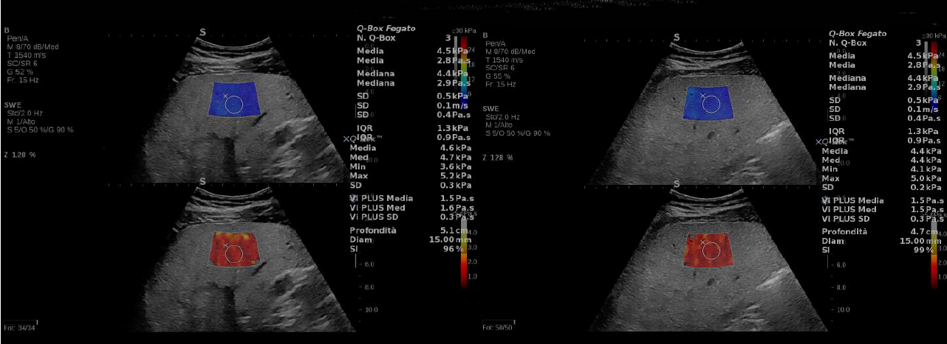

Supersonic "Aixplorer Ultimate, Mach30"

Mindray " Resona , Consona ,Portatili"

Sonoscape

Wisonic

FujiFilm Hitachi Aloka Arietta 650-750-850